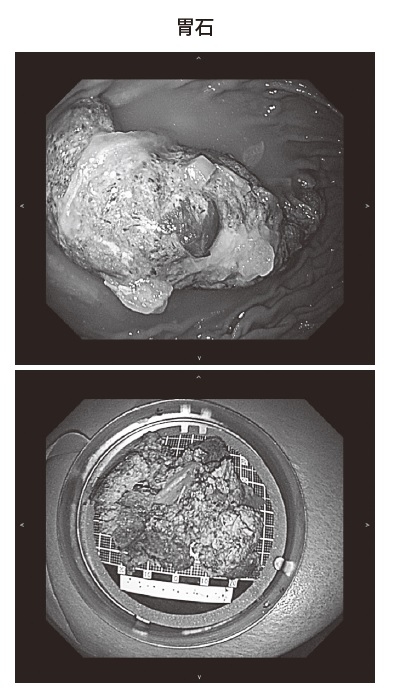

発見される胃石というのは5㎝から7、8㎝ぐらいの大きさはあると思います。

8㎝となりますと、かなり胃の内部を占めてしまいますね。

そうですね。内視鏡で見たら、胃の内腔は胃石で占められているといった状態になります。